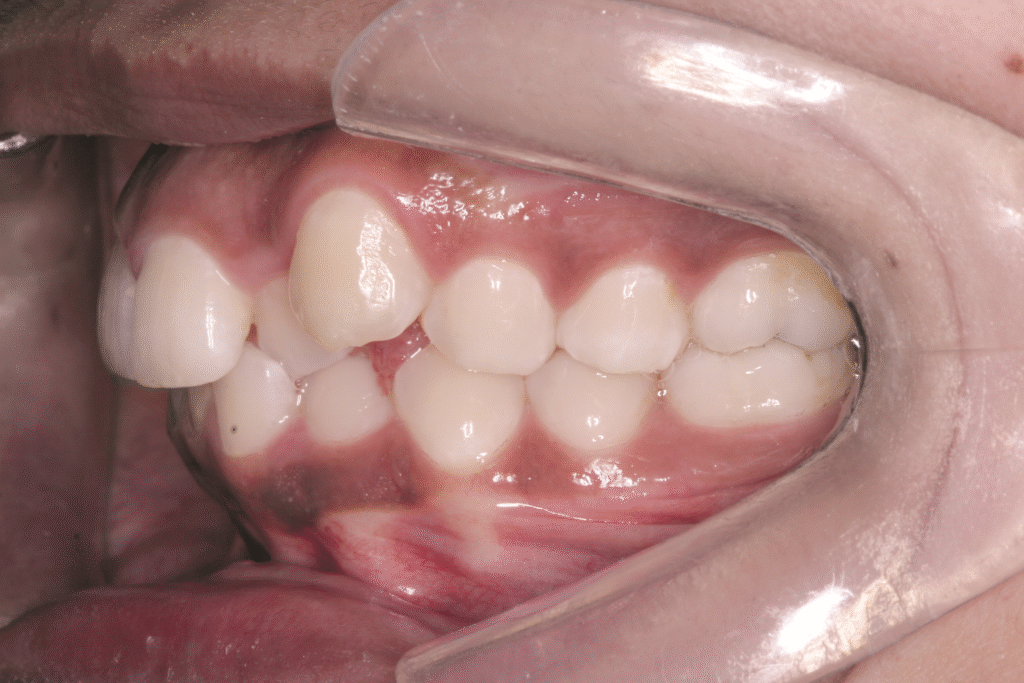

Existem vários conceitos contraditórios na literatura sobre o tratamento com extrações resultar em um perfil de tecido mole satisfatório ou não. O objetivo do presente artigo foi demonstrar a influência do ângulo nasolabial no tratamento da Classe II de Angle com exodontia de pré-molares superiores e inferiores. A paciente com 28 anos apresentava perfil facial convexo com assimetria facial, arco atrésico, grande apinhamento dentário e má-oclusão Classe II 1°, divisão de Angle, com desvio de linha média inferior para a esquerda e ângulo nasolabial inicial de 110°. Foi instalado um aparelho da técnica lingual Incognito, da 3M, com exodontia dos primeiros pré-molares superiores e inferiores de ambas as arcadas, e utilização de mini-implante ortodôntico. O tratamento ortodôntico obteve melhora do perfil labial, selamento passivo, abertura do arco do sorriso e melhora no perfil facial. Foi atingida simetria da linha média, correção dos apinhamentos e correção para Classe II de Angle e ângulo nasolabial de 114°. Conclusão: houve ganhos positivos para o perfil facial da paciente.

There are several contradictory concepts in the literature about whether treatment with extractions results in a satisfactory soft tissue profile, or not. The aim of this article is to demonstrate the influence of the nasolabial angle in the treatment of Angle Class II with upper and lower premolar extraction. The 28 years-old patient presented a convex facial profile, absence of facial asymmetry, atresic arch, large tooth crowding and Angle Class II Division 1 malocclusion with inferior midline deviation to the left and initial nasolabial angle of 110°. An appliance using the lingual technique was installed with extraction of the first upper and lower premolars of both arches and used an orthodontic mini-implant. The orthodontic treatment resulted in an improvement in the lip profile, passive sealing, opening of the smile arc and an improvement in the facial profile. Midline symmetry, crowding correction and correction for Angle Class II and 114° nasolabial angle were achieved. Conclusion: there were positive gains for the patient’s facial profile.